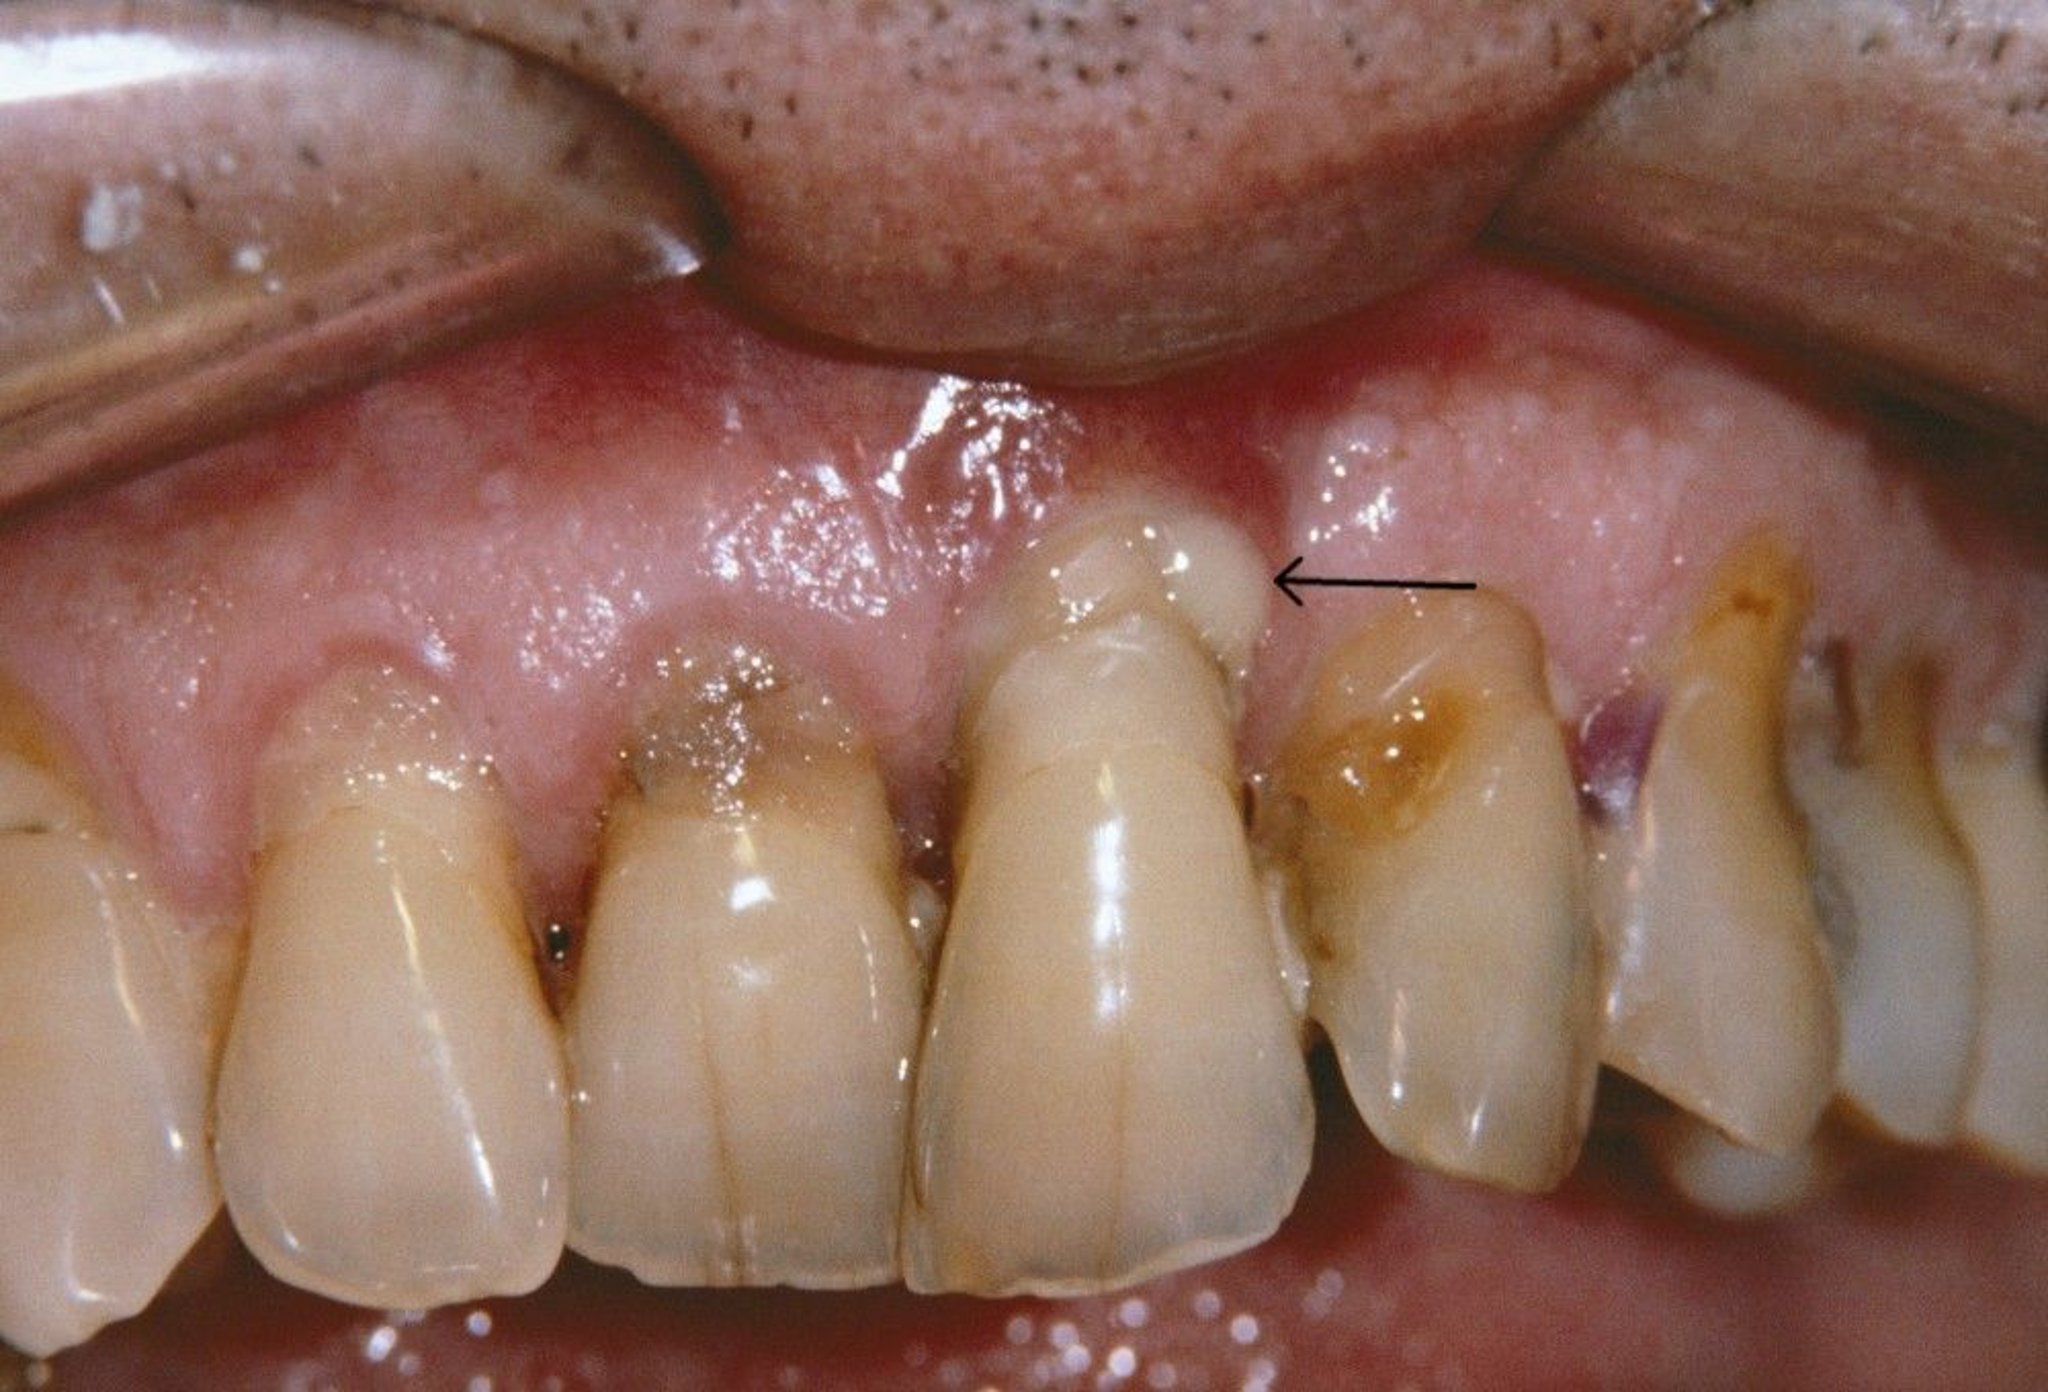

This photo shows receding gums and a periodontal abscess (arrow) in a person who has periodontitis.